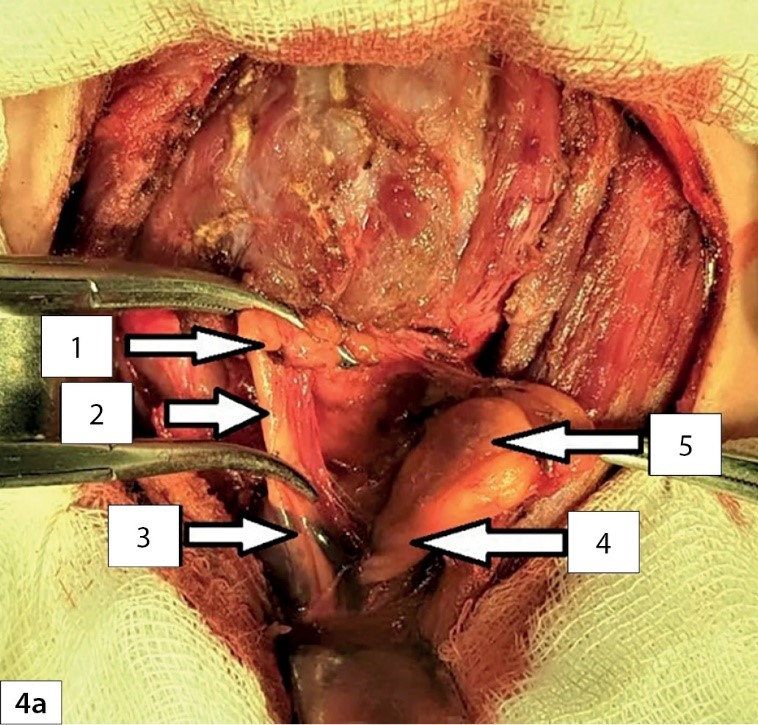

5. Рисунок 4а. Интраоперационная фотография. | |

Посмотреть

(165KB)